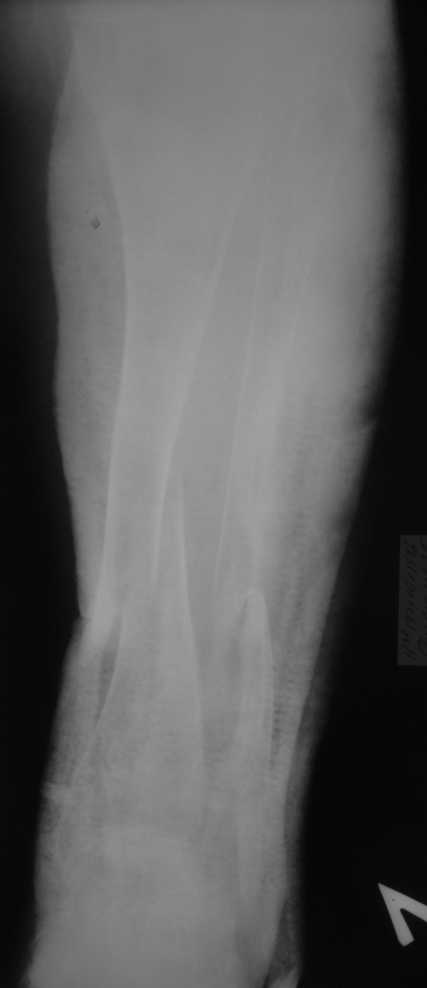

Но даже при малоинвазивной методике лечения применимой для даной больной существуют следующие проблемы: выраженный остеопороз, тонкий кортикал, очень широкий канал.

Контрольные рентгенограммы прилагаю.

Проблема в том, что в сагитальной плоскости угол голеней =30 градусам. Ширина канала 30.

Во-1-х, интрамедулярный остеосинтез относится к методам, дающим относительную, не абсолютную стабильность. Во-2-х, стабильность неплохо обеспечивается запирающими винтами. В-3-х, несоответствие кривизны стержня и канала приводит к повышению стабильности, в-4-х, канал можно искусственно сузить введением отклоняющих (трансмедуллярных, Poller) винтов.

Конечно, возможны - любые существующие. Но оптимальным из возможных здесь однозначно является закрытый интрамедуллярный остеосинтез.